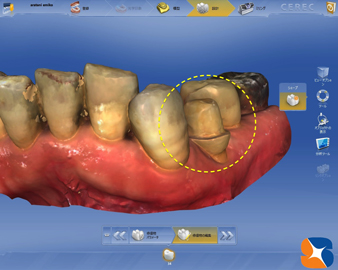

まず神経を残したままの銀歯を撤去。次は、オールセラミックの強度に合わせるため、歯を全周、均等にきっちりと切削しました。左(=写真=)は、スキャナーで画像を読み込む前の状態です。

まず神経を残したままの銀歯を撤去。次は、オールセラミックの強度に合わせるため、歯を全周、均等にきっちりと切削しました。左(=写真=)は、スキャナーで画像を読み込む前の状態です。

上記の状態を、スキャナーを使ってパソコンに読み込んだところ。実物は1㎝ 四方の歯が、PCに読み込むと、何百倍の画像に拡大されます。仕事の丁寧さ(綺麗に削れているか)が明確になります。

上記の状態を、スキャナーを使ってパソコンに読み込んだところ。実物は1㎝ 四方の歯が、PCに読み込むと、何百倍の画像に拡大されます。仕事の丁寧さ(綺麗に削れているか)が明確になります。